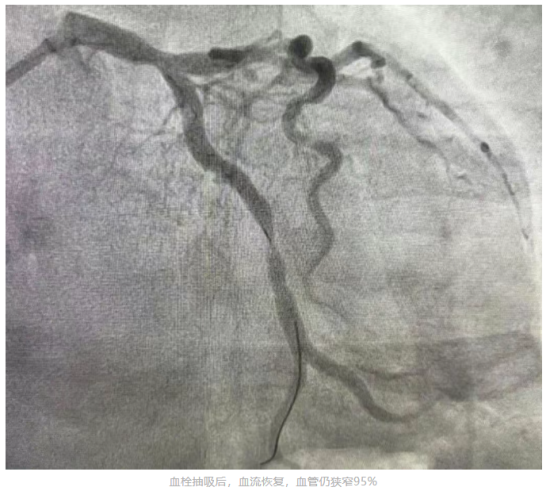

心血管内一科主任张国华到场后,结合患者心电图报告、临床症状及既往心脏病史,迅速诊断其为急性心肌梗死,并指导立即给予口服药物,建议其进行急诊冠脉造影检查及介入治疗开通血管。心血管内科介入团队迅速为李先生进行冠脉造影检查。检查结果显示,患者左冠状动脉回旋支完全闭塞,随时可能危及生命。经过血栓抽吸后血管开通,但病变处狭窄仍为95%。随后心血管内一科介入团队又为患者植入1枚支架。支架植入后患者病变狭窄完全消失,血流通畅,胸痛消失,意识状态恢复。